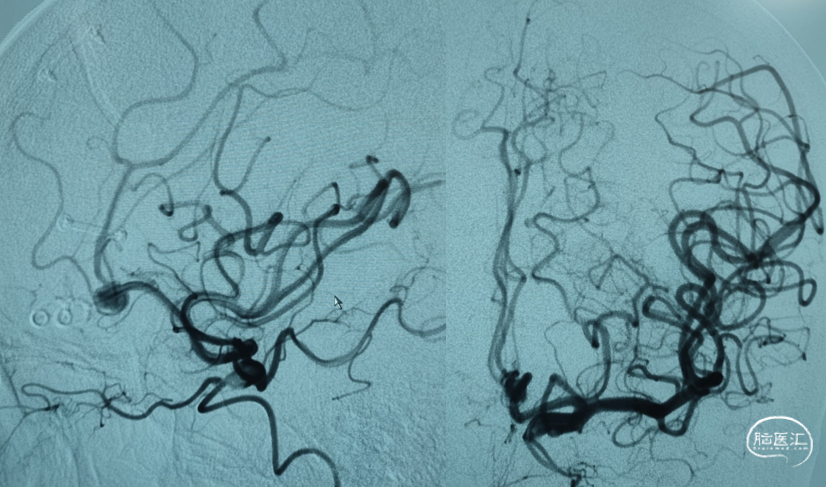

DSA

DSA

DSA:右侧颈内动脉后交通动脉起始段动脉瘤

DSA